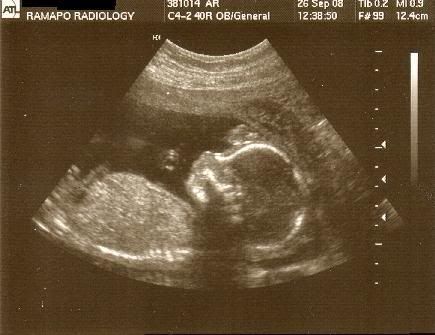

So, everything went very well with my little 's anatomy scan! He was wiggling up a storm. My Mom and Stepdad got to come in and see him too. Every organ and system is developing perfectly and he appears to be happy and healthy with 10 fingers and 10 toes! He's also measuring right on schedule.

So, without further adieu....here's my baby at almost 20 weeks (19 Weeks, 6 Days)